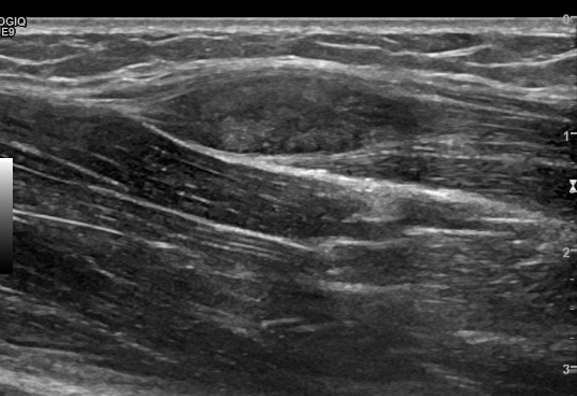

左侧前臂肌层可见低回声结节,大小约 2.3cm×0.8cm ,呈梭形,边界清楚,形态规则,回声欠均匀,可见少许血流信号(见图 1-2 )。

图 1 肿物二维声像图